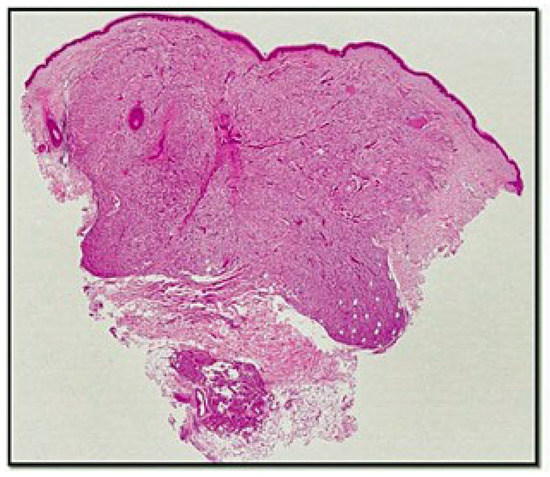

3. Results